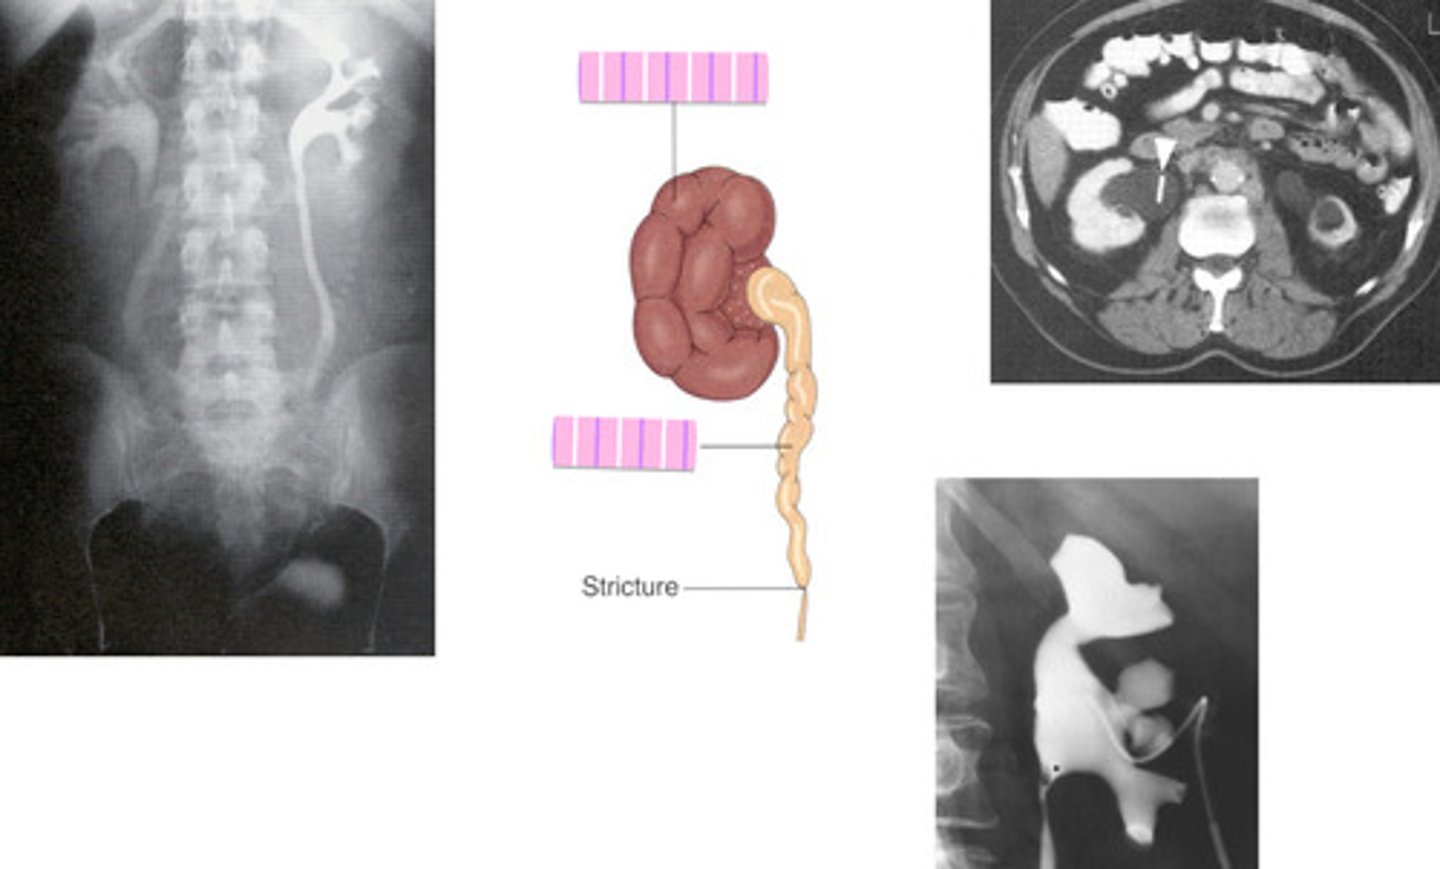

- Urinary Tract Obstruction

- Hydroureter and hydronephrosis

- CT, U/S, delayed IVU

- What pathology is caused by a stone, tumor, stricture, enlarged prostate, congenital anomaly, or pregnancy?

- What can happen to the ureters and kidneys?

- What imaging modalities are used to see this pathology?

Hydronephrosis

What is the condition where one or both kidneys become stretched and swollen as the result of a build-up of urine inside them?